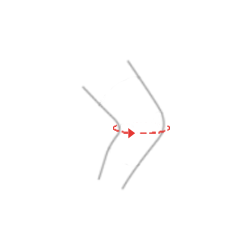

Konstrukcja ortezy jest projektem unikatowym, łączącym w sobie zarówno funkcje ortez otwartych – łatwość zakładania wyrobu poprzez brak konieczności wciągania ortezy przez stopę, jak również zamkniętych – pełna stabilizacja rzepki i stawu kolanowego. W tym celu w wyrobie zainstalowano anatomicznie ukształtowany pierścień rzepki.

Ortezę OKD-06 wyposażono w dwa komplety pasów obwodowych oraz plastikowe uchwyty szyn ortopedycznych. W wyrobie zastosowano nowatorskie, profilowane szyny 1R orthodesign z regulacją kąta zgięcia i wyprostu co 15 stopni.